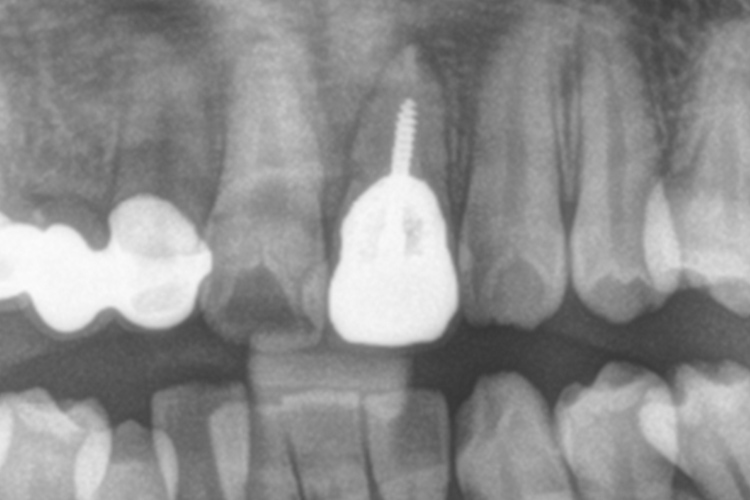

治療前

移植歯

移植後

補綴装着

抜歯・移植前

抜歯・移植後固定中

固定後・ブリッジ完成